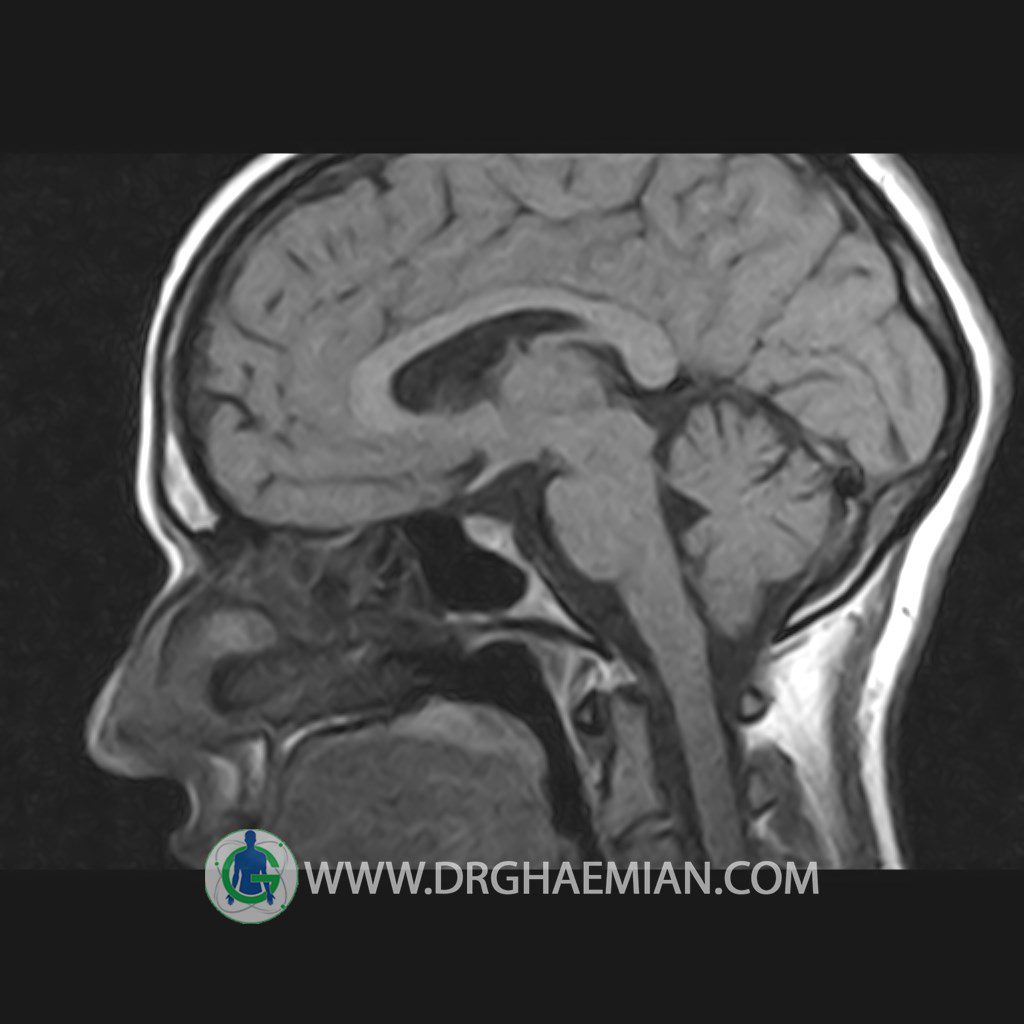

پزشکان اغلب از تصویربرداری ام آر آی برای تشخیص و درمان عارضه های پزشکی که فقط با استفاده از اشعه ایکس یا میدان مغناطیسی و امواج رادیویی قابل مشاهده است، استفاده می کنند. دستگاه ام آر آی تصاویر دقیق از ساختار های داخلی بدن ایجاد می کند. در این کیس هیپرپلازی هیپوفیز و آدنوم مشاهده می شود.

HYPOPHYSIS MRI

(with and without contrast)

Technique: Axial , coronal T1 , Axial , coronal , sagittal T2 , Axial, coronal T1 post Gd & 64 dynamic thin coronal slices.

REPORT :

The sella shows normal size , position and configuration .

The borders of its floor and walls are smooth and sharply defined .

The infundibulum is centered and of normal size .

The optic chiasm and suprasellar spaces appear normal .

The cavernous sinus and imaged portions of the internal carotid artery and carotid siphon are unremarkable .

Evaluable portions of the neurocranium show no abnormalities .

The sphenoid sinus is clear and pneumatized .

– Mild convexity at superior border of pituitary gland with post contrast homogeneous enhancement suggestive for pituitary hyperplasia & iso signal adenoma

is seen